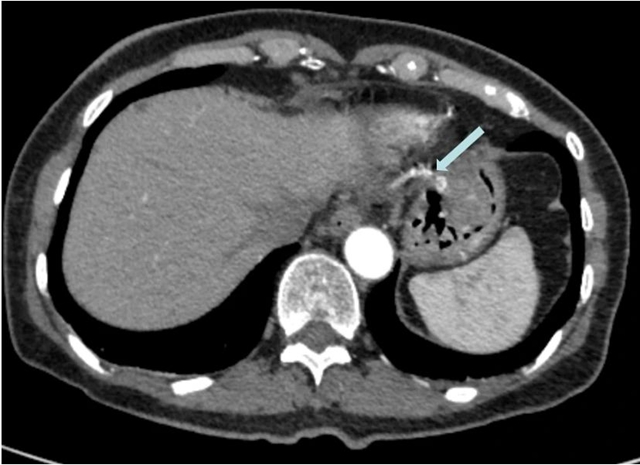

腹部增强CT提示瘤体有一根较大动脉供血,箭头示动脉血管

如何为患者实施安全有效的切除方案成为该团队面临的难题。当时有两个备选方案:内镜下微创治疗或外科腹腔镜下切除肿瘤。这两种方案均有弊端,为瘤体提供“营养补给”的胃左动脉分支血管较粗,贸然进行内镜微创治疗,术中容易发生大出血,风险高。倘若选择外科手术,需要切除患者的部分胃,创伤较大,且影响患者术后生活质量,显然也不是最好的选择。

“科室团队进行了充分讨论,在取得家属的同意后,决定分两步走,先由科室的介入团队(朱清亮主治医师与张海龙博士)进行胃黏膜下肿物介入栓塞治疗,‘堵塞’患者胃左动脉分支血管,将肿瘤‘饿死’。隔一段时间后,再由汤小伟副教授进行内镜下ESD切除术剥离肿瘤。”汤小伟副教授说,这是消化内科的一次有益尝试,在国内也并不多见。